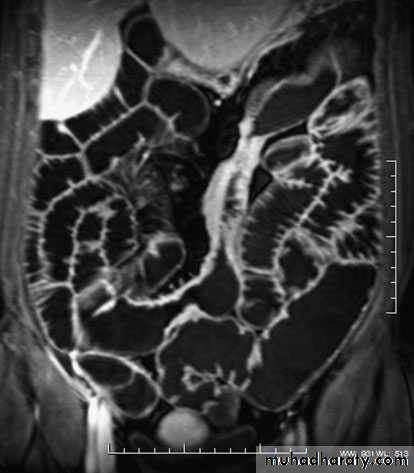

ImagingBarium enema will show similar features to those of colonoscopyin the colon. The best investigation of the small intestine is smallbowel enema . This will show up areas of delay anddilatation. The involved areas tend to be narrowed, irregular and,sometimes, when a length of terminal ileum is involved, theremay be the string sign of Kantor. Sinograms are useful in patientswith enterocutaneous fistulae. CT scans are used in patients withfistulae and those with intra-abdominal abscesses and complexinvolvement .Magnetic resonance imaging (MRI) has been shown to be usefulin assessing perianal disease.